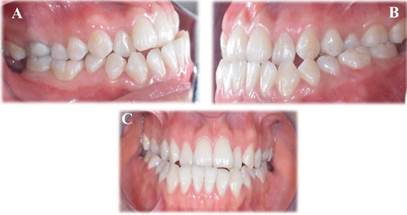

Descripción de caso clínico, paciente mestizo de sexo femenino, de 19 años de edad, llega a consulta, en la primera cita, se identificó clínicamente un prognatismo mandibular y una asimetría facial evidente en la paciente (Figura 1). Para confirmar y complementar el diagnóstico, se solicitaron estudios de imagen, consistentes en una radiografía panorámica, un análisis cefalométrico y una serie de fotografías intraorales y extraorales (Figura 1, Figura 2 y Figura 3).

Figura 2 Fotografías intraorales A: Oclusión Vista lateral derecha B: Oclusión Vista lateral izquierda C: Oclusión vista frontal

Asimismo, mediante la radiografía panorámica se confirmó la presencia de una laterognasia mandibular hacia el lado derecho, responsable de la asimetría facial marcada en la paciente. Estos hallazgos fueron determinantes para planificar el abordaje ortodóncico y quirúrgico adecuado. Se empleó un flujo digital para el diagnóstico y la planificación del tratamiento, lo cual incluyó la integración de escaneos intraorales, y análisis cefalométricos digitales. Esta tecnología permitió una evaluación tridimensional precisa de las estructuras óseas y dentales, facilitando un diagnóstico más detallado y la simulación del plan quirúrgico y ortodóntico, asegurando una mayor predictibilidad en los resultados clínicos.

Posterior a un año de tratamiento ortodóntico postquirúrgico, se evidencian resultados clínicos significativos en la paciente, una correcta alineación y nivelación de las arcadas dentarias con una notable oclusión funcional. La relación molar y canina se ha estabilizado, alcanzando un equilibrio oclusal contribuyendo a la funcionalidad masticatoria. Una mejora notable de la asimetría facial disminuyendo considerablemente, reflejando una armonía facial mejorada, gracias a la corrección del prognatismo mandibular y la reposición ósea lograda con la cirugía ortognática. La paciente reporto una notable mejora en la función masticatoria y en la estética facial, lo que ha contribuido a su calidad de vida (Figura 6).